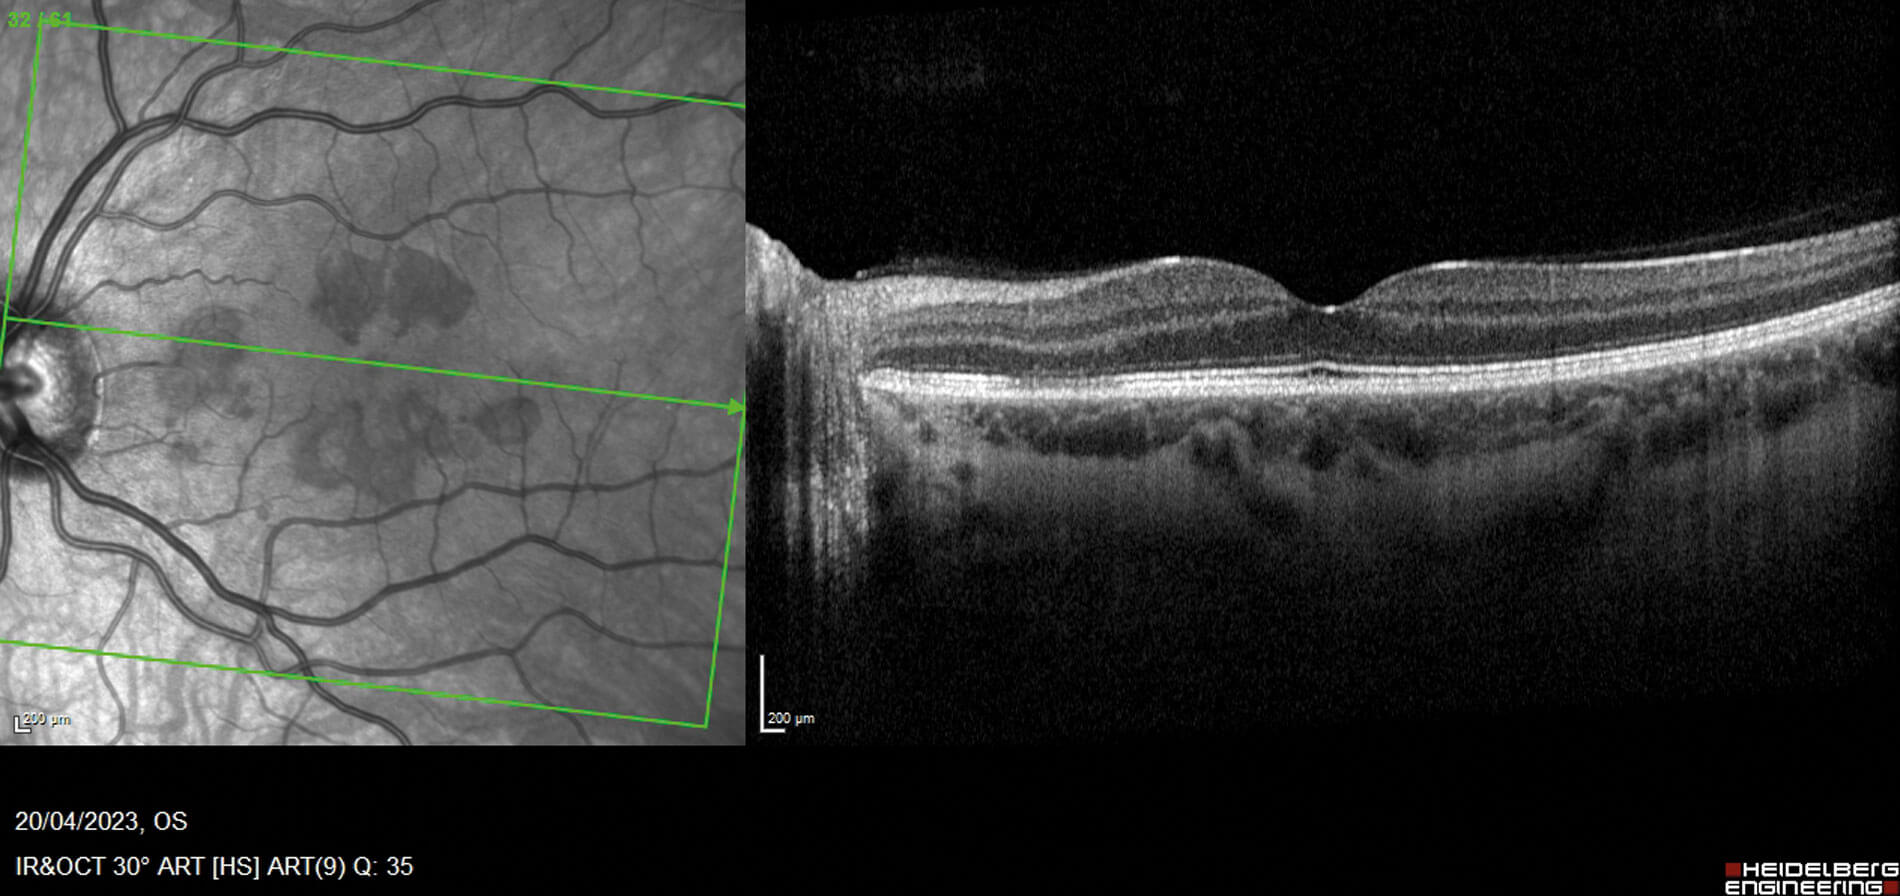

Figures 1a (top) and 1b (bottom): OCT macular view, showing hyper-reflectivity in the outer nuclear layer, with associated focal signal reduction of the inner segment / outer segment junction in the left eye (a) and right eye (b). Near infrared pictures show corresponding areas as mostly petaloid lesions, pointing towards the fovea.

Fundoscopy showed evidence of discrete foveal reflex changes, which on further evaluation with optical coherence tomography (OCT) macular view showed multiple areas of outer retinal disruption (see Figures 1a and 1b). Optical coherence tomography angiography displayed evidence of reduced flow in the deep retinal plexus, consistent with ischaemia (Figures 2a and 2b). These retinal imaging findings correlated with the patient’s subjective visual changes, as noted on their Amsler grid drawings (see Figures 3a and 3b).